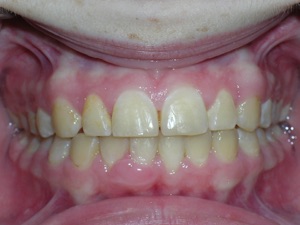

Here’s a fascinating case of a young lady who had a completely blocked out premolar.

With a combination of braces, expansion and trimming we were able to bring it in. Watch!

Here are the results.